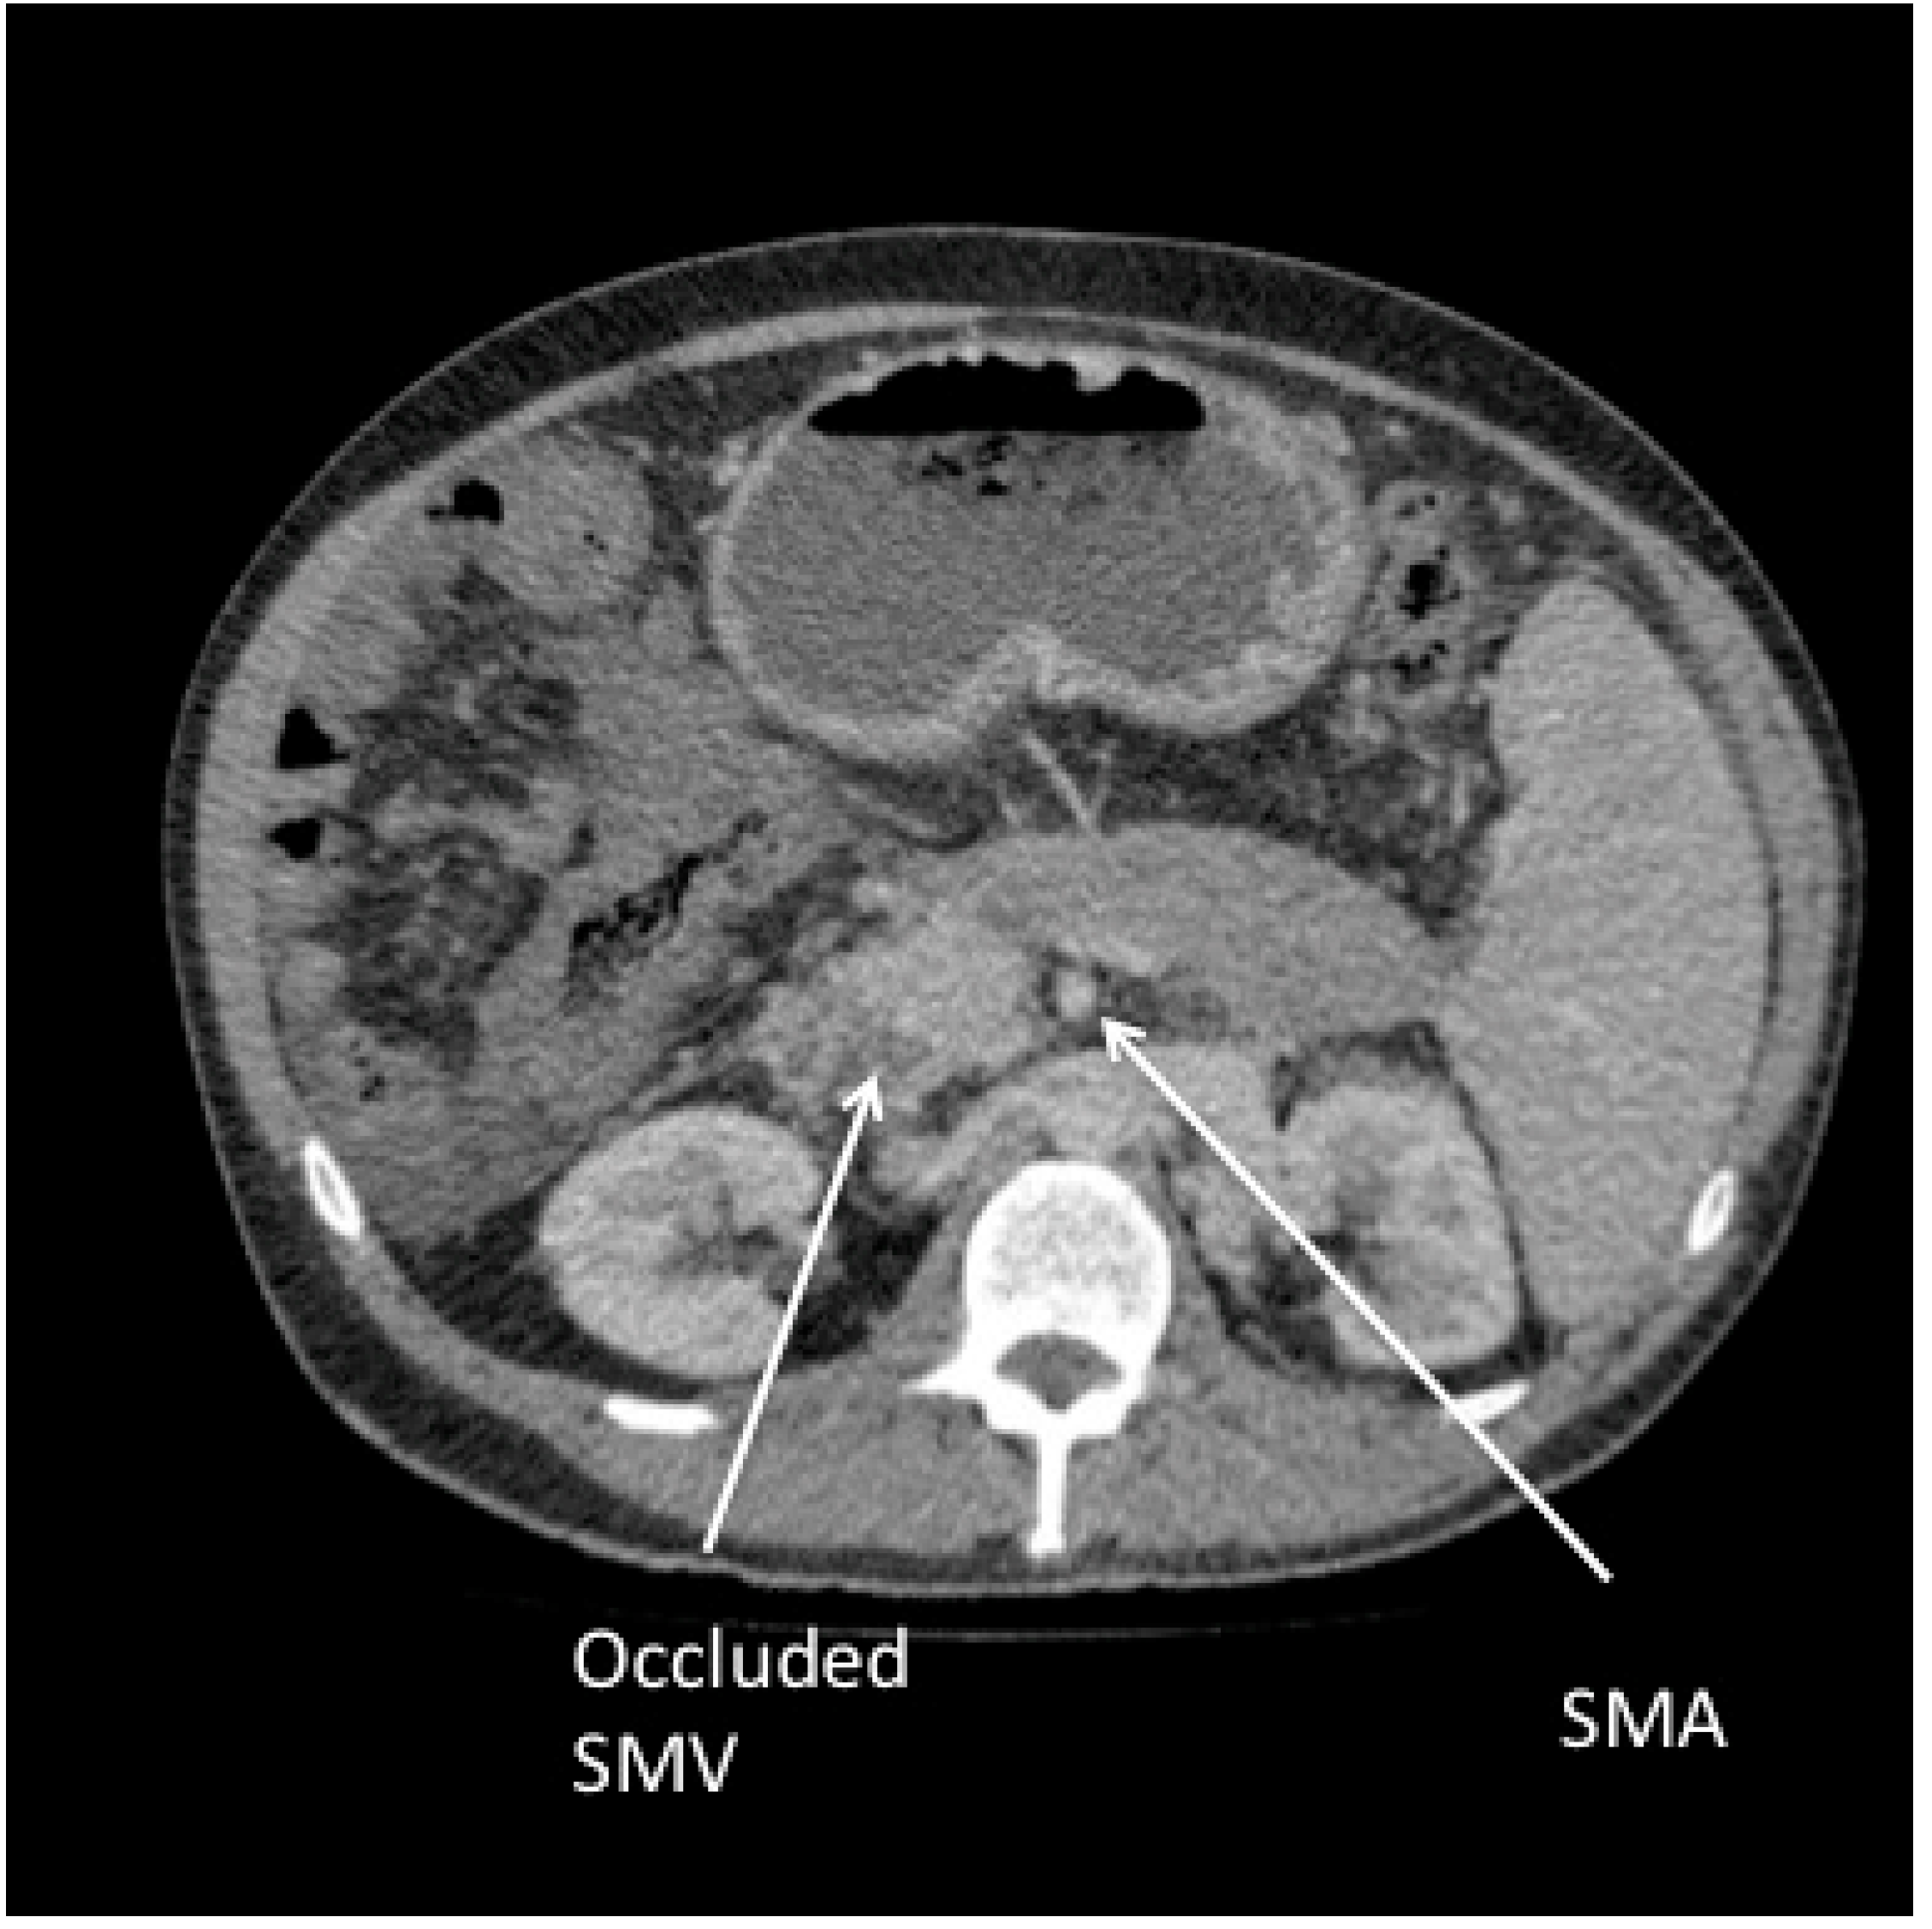

A CT scan showed further extension of the thrombus (Figure 2) and, after discussion with a quaternary centre, the Sengstaken Blakemore was maintained until the patient could undergo a surgical shunt. Anatomical considerations (thrombus in the portal, splenic and mesenteric veins) made this technically difficult and following initial stabilisation, splenectomy with oesophageal devascularisation was considered the best alternative treatment. The patient suffered a further massive haemorrhage and, despite resuscitative efforts, died from bleeding before they could perform the procedure.

Figure 2. CT image showing extension of thrombus into the superior mesenteric vein (SMV) adjacent to the superior mesenteric artery (SMA).